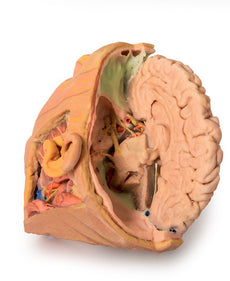

Posterior view of the pharynx: The superior, middle and inferior pharyngeal constrictors are indicated on the pharynx wall. The oesophagus can be identified emerging from the lower end of the pharynx. The posterior horn of the hyoid bone acts as a useful landmark. The carotid sheath seen from behind clearly shows the vagus nerve and its pharyngeal branches on the left. The recurrent laryngeal nerve is briefly visible on the left lying medial to the inferior thyroid artery. The occipital arteries are visible as they curve around the mastoid process. The vertebral arteries are seen either side of the brainstem as they enter the foramen magnum. The cerebellum has been removed to allow the fourth ventricle to be exposed. The cut surfaces of the cerebellar peduncles are clearly visible. A large portion of the posterior inferior cerebellar artery on the right is still visible as it winds around around the brainstem.

Cranial Cavity: The left and right orbits have been opened to reveal the orbital nerves and vessels along with the eyes and optic nerves. The optic chiasm, optic tracts and the lateral geniculate bodies are retained thus showing a large part of the visual pathways. The brainstem is cut at the level of the superior colliculi on the left and slightly lower on the right. The olfactory tracts and bulbs are also demonstrated. The origins of many of the cranial nerves from the brainstem are clearly visible.

Posterior view of the pharynx: The superior, middle and inferior pharyngeal constrictors are indicated on the pharynx wall. The oesophagus can be identified emerging from the lower end of the pharynx. The posterior horn of the hyoid bone acts as a useful landmark. The carotid sheath seen from behind clearly shows the vagus nerve and its pharyngeal branches on the left. The recurrent laryngeal nerve is briefly visible on the left lying medial to the inferior thyroid artery. The occipital arteries are visible as they curve around the mastoid process. The vertebral arteries are seen either side of the brainstem as they enter the foramen magnum. The cerebellum has been removed to allow the fourth ventricle to be exposed. The cut surfaces of the cerebellar peduncles are clearly visible. A large portion of the posterior inferior cerebellar artery on the right is still visible as it winds around around the brainstem.

Cranial Cavity: The left and right orbits have been opened to reveal the orbital nerves and vessels along with the eyes and optic nerves. The optic chiasm, optic tracts and the lateral geniculate bodies are retained thus showing a large part of the visual pathways. The brainstem is cut at the level of the superior colliculi on the left and slightly lower on the right. The olfactory tracts and bulbs are also demonstrated. The origins of many of the cranial nerves from the brainstem are clearly visible.